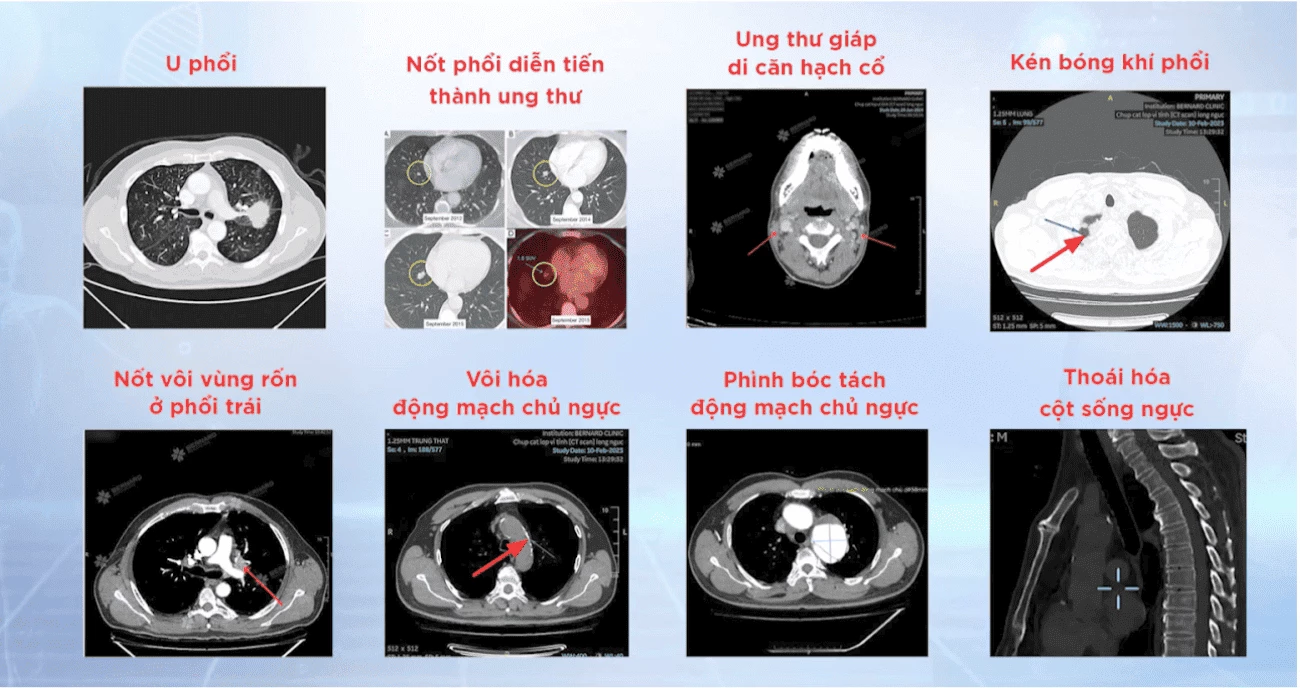

Những tổn thương được phát hiện qua chụp MRI tại Bernard

CT scan với khả năng tái tạo bộ phận, mô, xương trong cơ thể thông qua hình ảnh các lát cắt hoặc mặt cắt ngang của cơ thể cơ thể người chi tiết và chính xác, hỗ trợ bác sĩ phát hiện sớm các tổn thương dù rất nhỏ trong phổi mà các phương pháp như chụp X-quang không thể nhìn thấy

Hình ảnh học từ CT toàn thân giúp bác sĩ quan sát rõ tổn thương bên trong cơ thể mà mắt thường hay khám lâm sàng không thể thấy được

Hệ thống CT Scan được Bernard tận dụng triệt để trong tầm soát và phát hiện sớm các tổn thương lành tính; Tổn thương tiền ung thư (phổi, gan, vú, giáp, cổ tử cung, dạ dày, đại trực tràng,...); Ung thư giai đoạn sớm và ung thư (trích xuất từ hệ thống PACS tại Bernard)

Ngoài khả năng phát hiện ung thư phổi, CT Scan còn giúp phát hiện các bất thường trong ổ bụng với độ chính xác 95%. Các bác sĩ sử dụng CT để phân tích gan hoặc tuyến tụy, túi mật, bàng quang, khối u thận - Viêm đại tràng, viêm ruột, viêm ruột thừa - Sỏi thận, sỏi bàng quang, các tổn thương nội tạng (trích xuất từ hệ thống PACS tại Bernard)